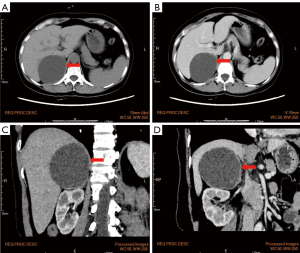

To evaluate the right adrenal mass, the patient underwent an adrenal ultrasound and computed tomography (CT) scans following admission. Ultrasound findings revealed a heterogeneous hypoechoic lesion in the right adrenal region, measuring approximately 8.0 cm × 6.5 cm, with well-defined boundaries and an irregular shape (Figure 2A). The blood flow signal within the lesion was classified as Adler grade 0 (Figure 2B), suggesting a benign adrenal tumor, most likely an adenoma. CT imaging (Figure 3) revealed a rounded low-density mass in the right adrenal gland with clear boundaries and smooth margins (Figure 3A,3C), measuring approximately 7.9 cm × 8.6 cm. The mass exhibited mild enhancement on contrast imaging (Figure 3B,3D), and the CT findings were consistent with a benign tumor, with differential diagnoses including adenoma and ganglioneuroma.

ACL shares similarities with other adrenal lymphangiomas, as it typically presents with few abnormalities in history, symptoms, signs, and adrenal hormone levels, with preoperative diagnosis primarily relying on imaging studies. In the present case, the patient exhibited a low testosterone level, which normalized postoperatively. After analysis, we surmise that this might be attributed to the tumor’s pressure on surrounding tissues or its effect on adrenal blood flow, which could interfere with hormone synthesis. While the adrenal gland primarily produces corticosteroids and catecholamines, tumors can also indirectly affect testosterone levels. The widespread use of ultrasound is crucial for detecting adrenal lesions. Herein, the preoperative ultrasound revealed a heterogeneous hypoechoic mass without significant cystic features, likely due to the small size of the ACL’s cystic spaces and sponge-like characteristics. CT imaging is the preferred method for preoperative diagnosis of adrenal lymphangiomas, typically showing a unilocular, round or oval structure, often revealing cyst walls and septations. Our CT findings indicated a rounded low-density adrenal mass without septations and mild enhancement, suggesting a small cystic cavity in the ACL. The imaging findings from the external hospital MRI and our hospital CT were inconsistent with the final pathological results, highlighting the limitations of imaging in diagnosing rare or complex lesions. Clinically, integrating multiple imaging modalities is warranted to obtain more comprehensive diagnostic information and improve the accuracy of preoperative assessment.

Preoperative differentiation of ACL from other adrenal adenomas, cystic changes in adrenal tumors, and renal cysts is essential. Adrenal adenomas typically appear as low-density masses in the adrenal region, usually less than 4 cm in diameter. A key feature of adenomas is their fat content, which can often be detected on CT using fat-suppression sequences. Cystic changes in adrenal tumors are most commonly seen in pheochromocytomas, which frequently show central hemorrhage and necrosis as the main pathological features (6,7). Besides, pheochromocytomas usually present with endocrine symptoms. Adrenal cysts typically appear as thin-walled, uniformly low-density lesions with well-defined borders and no enhancement, with uniformity and low density being their primary characteristics (8). In contrast, the present case was characterized by a multilocular, vascularized appearance with enhancement patterns visible on contrast imaging. Although imaging studies are crucial for diagnosing ACL, their lack of specificity and potential for misleading features (9) still warrant pathological examination for a definitive diagnosis.